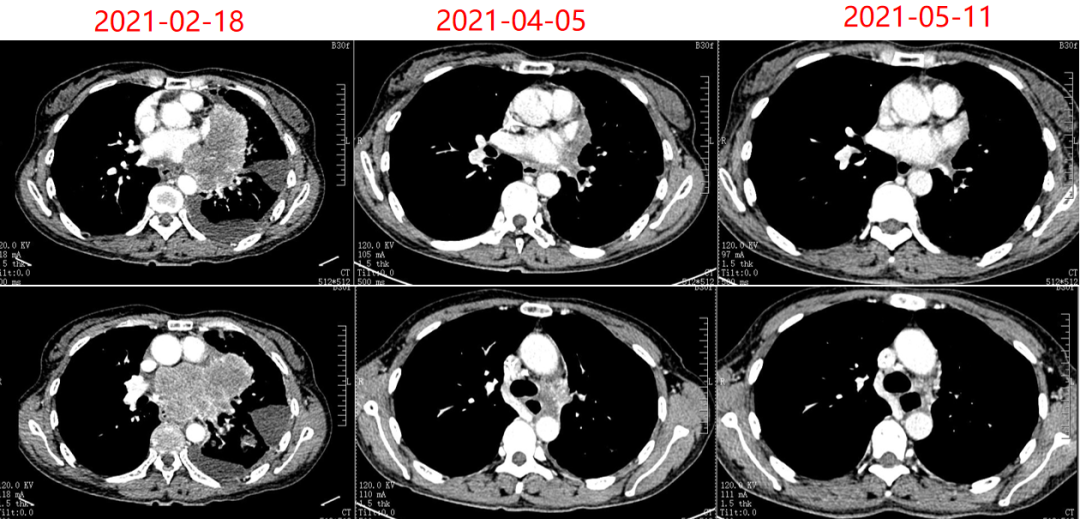

联合或不联合替雷利珠单抗用于未经治疗ES-SCLC患者的疗效及安全性的随机、双盲、安慰剂对照的Ⅲ期RATIONALE-312研究。患者于2021年2月22日接受首次治疗后,肿瘤快速缓解,第一次评疗效估即达到PR。此后经定期影像学随访评估,疗效持续维持,PFS已超过40个月。在整个治疗过程中,患者总体安全性可控,生活质量良好。

图3. CT复查结果

病例一患者为45岁女性,因“胸闷”于2020年1月就诊。经影像学检查、病理检查

确诊为广泛期小细胞肺癌(cT4N3M1a,ⅣA期)。患者因经济因素入组RATIONALE-312研究,于2021年2月22日起接受研究方案(铂类+依托泊苷联合替雷利珠单抗或安慰剂)治疗。治疗后肿瘤快速缓解,首次疗效评估即达到PR。此后定期进行影像学随访,结果显示疗效持续,病灶控制稳定,PFS已超过40个月,且治疗期间总体安全性可控。